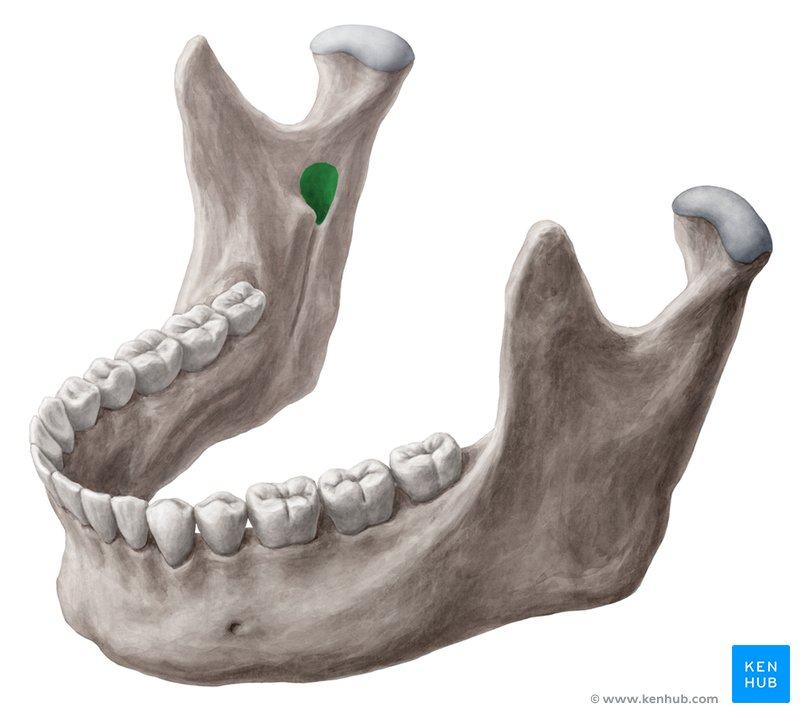

what is this, its description and its appearance on images- 1st line

lingula

small tongue shaped projection seen adjacent to mandibular foramen

radiopacity, not seen intraoral